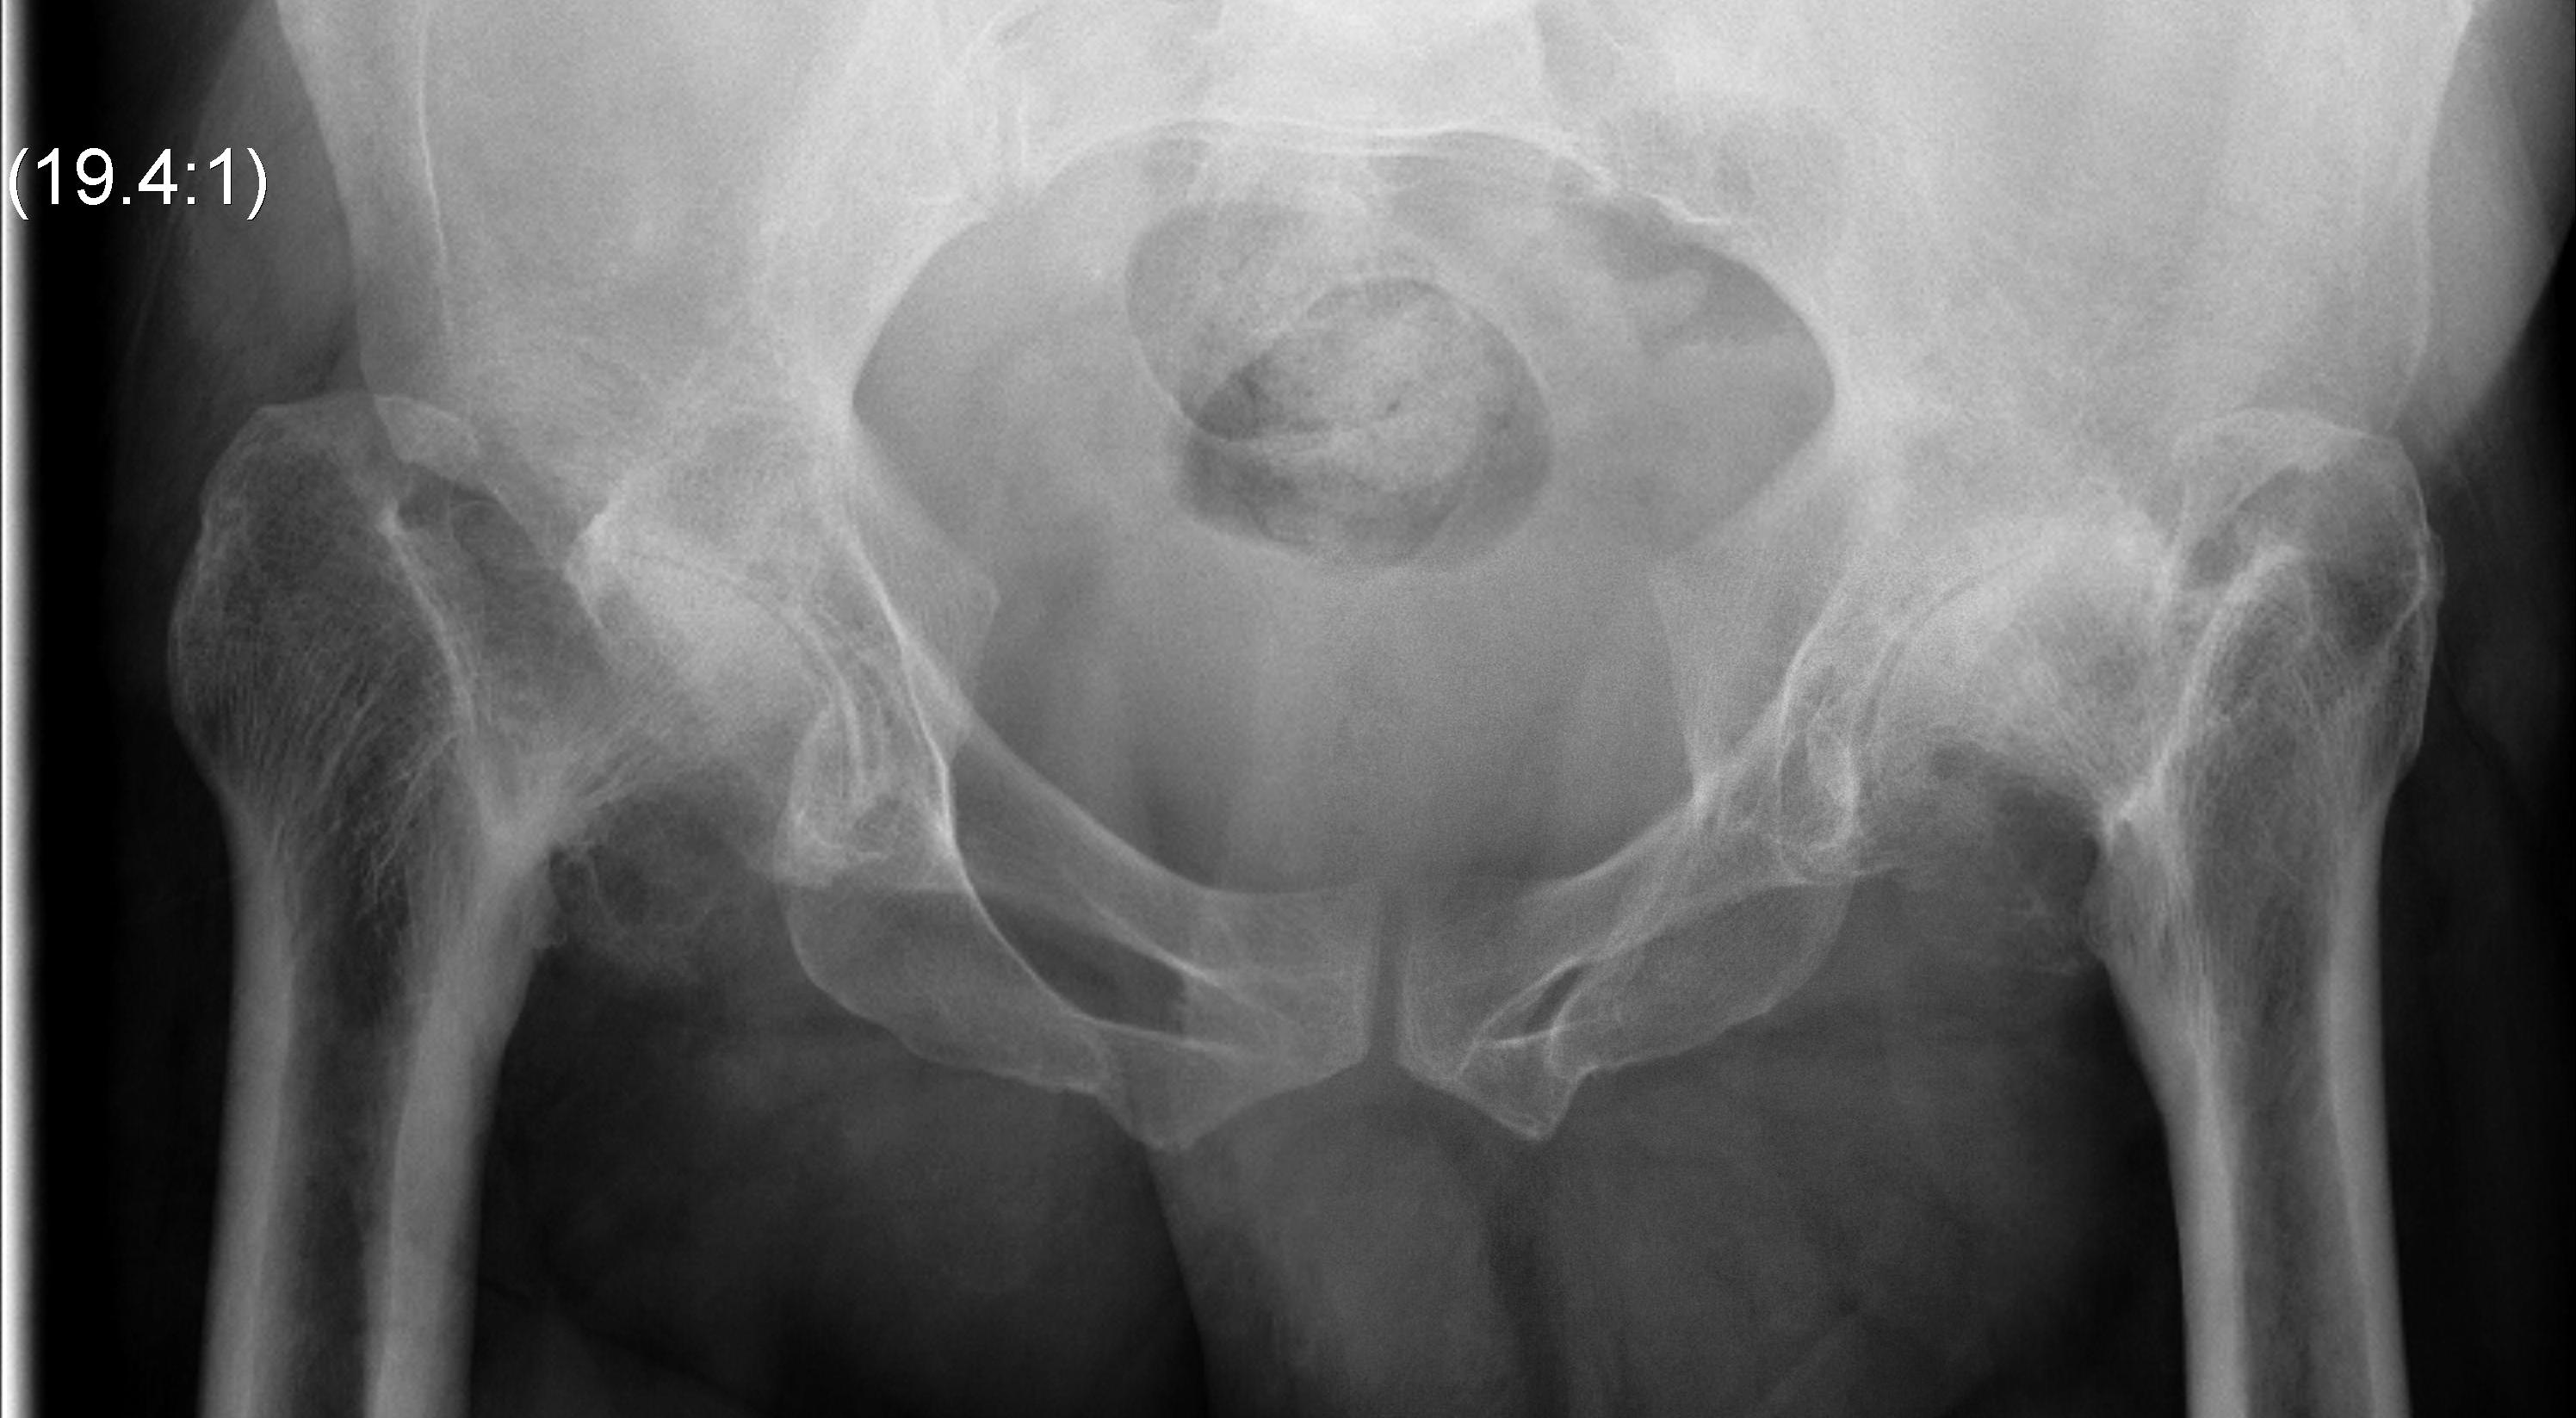

Incidence

- incidence of OA after Perthes

- nonoperative treatment: 23% THA at 40 years

- operative treatment: 18% THA at 40 years